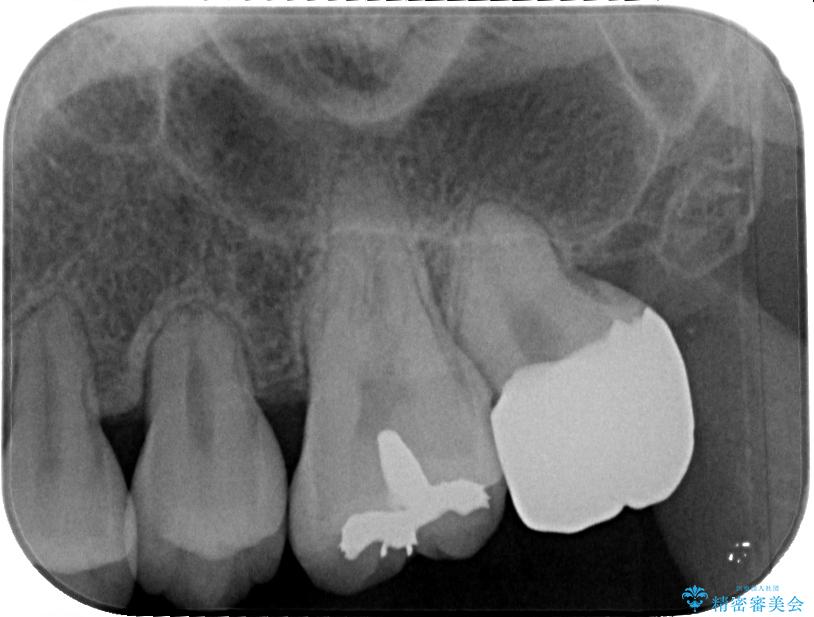

セラミッククラウンの適合はレントゲン写真からも分かる通り、境界がぴったりと合った、高適合のものとなりました。